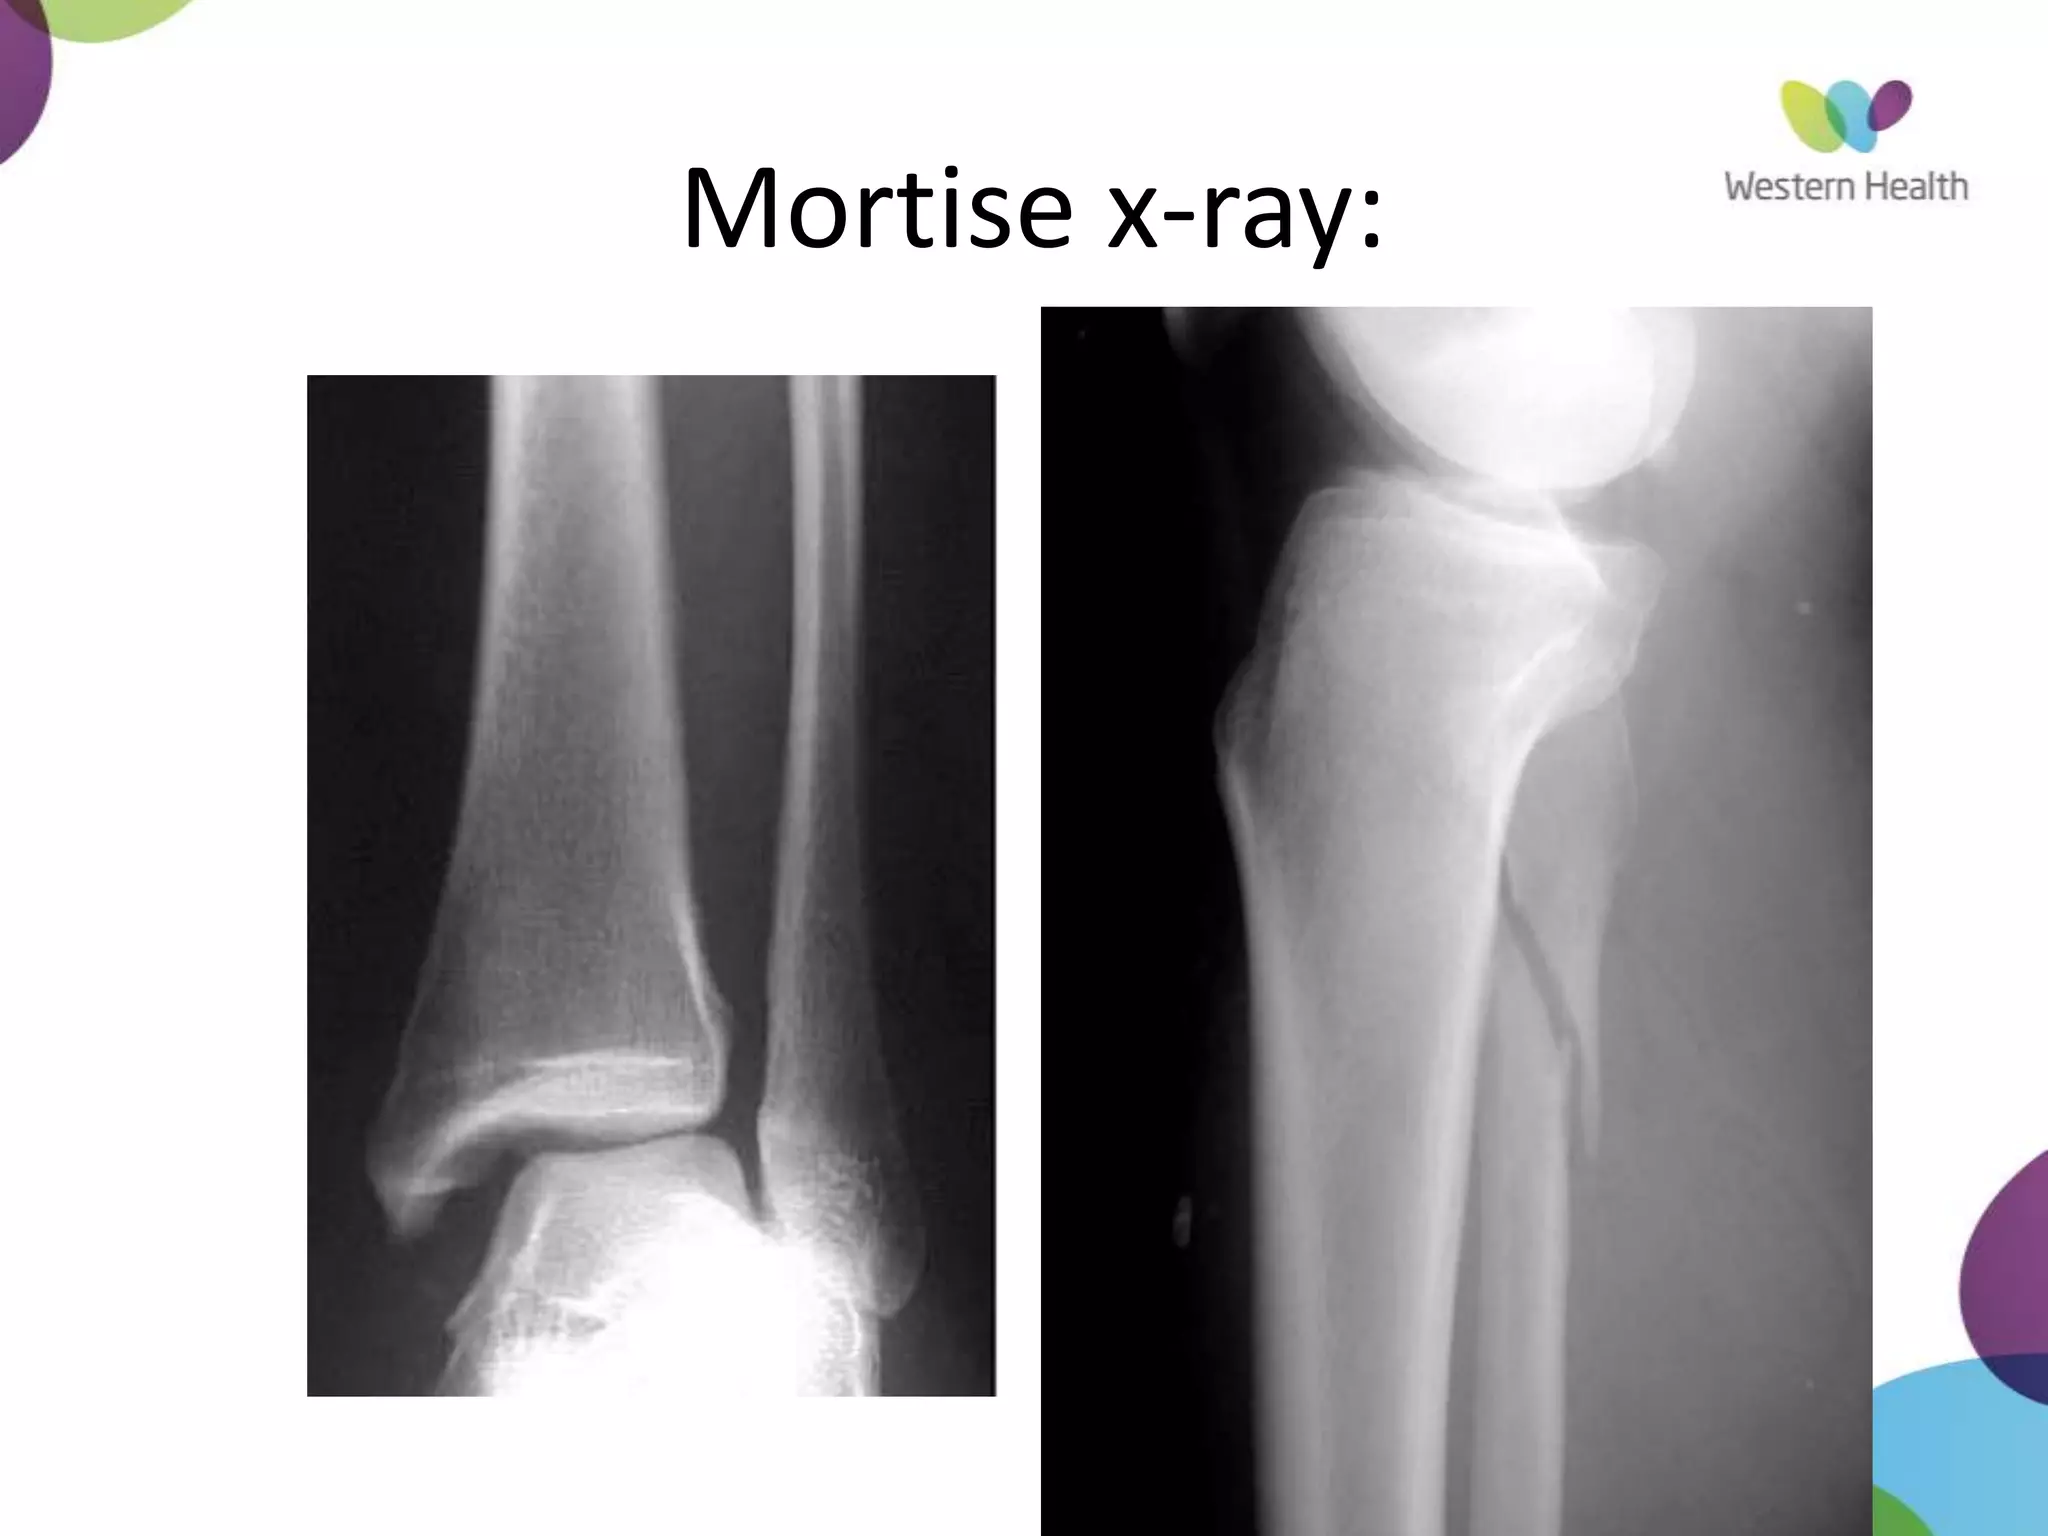

Mortise X-Ray

• ankle in 15-25° of IR

• Medial clear space

– Between lateral border of

medial malleous and medial

talus

– <4mm is normal

– >4mm suggests lateral shift

of talus

Mortise x-ray: